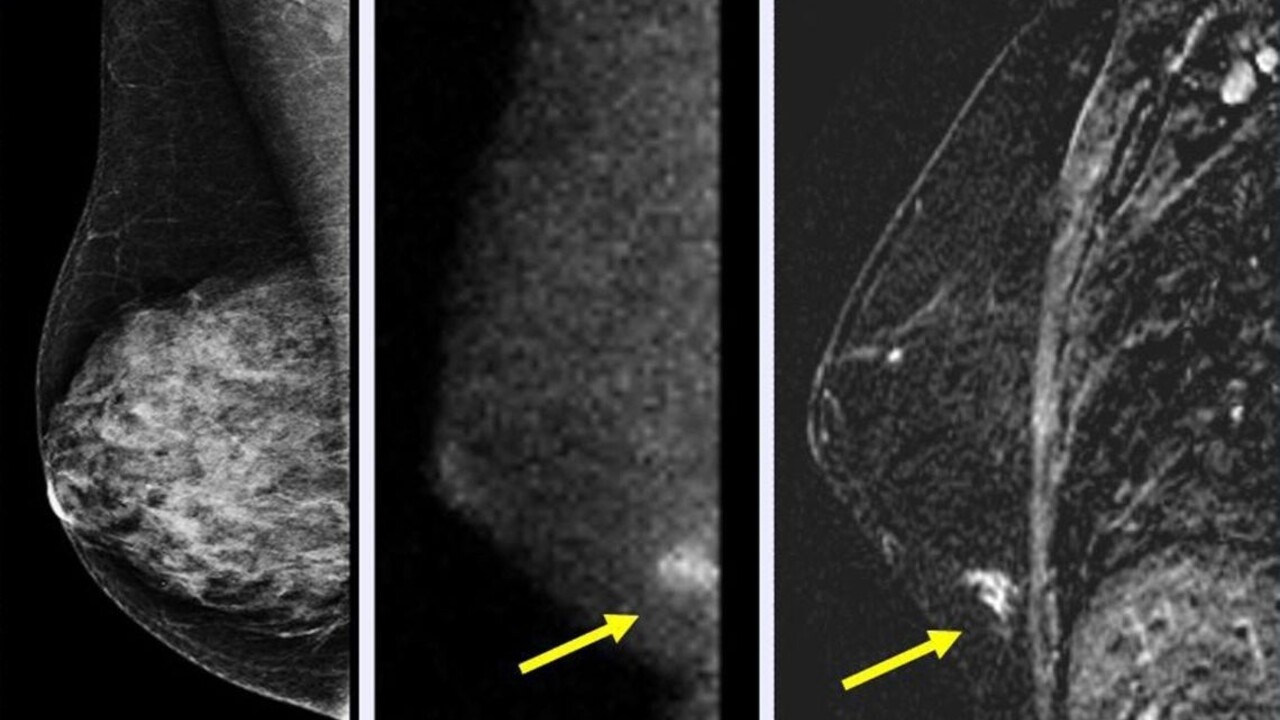

Ako uviedla výkonná riaditeľka Ligy proti rakovine Eva Kováčová, v rámci Slovenska pribúda každoročne vyše 30 000 ľudí s rakovinou. Podľa Národného centra zdravotníckych informácií patria medzi najrizikovejšie diagnózy na Slovensku zhubný nádor hrubého čreva, a to rovnako u mužov, ako aj u žien. Najčastejšou diagnózou u žien je karcinóm prsníka, nasleduje kolorektálny karcinóm a karcinóm maternice. U mužov je najčastejší kolorektálny karcinóm, nasleduje zhubný nádor pľúc a prostaty. Nádorové ochorenia postihujú viac ženy ako mužov.